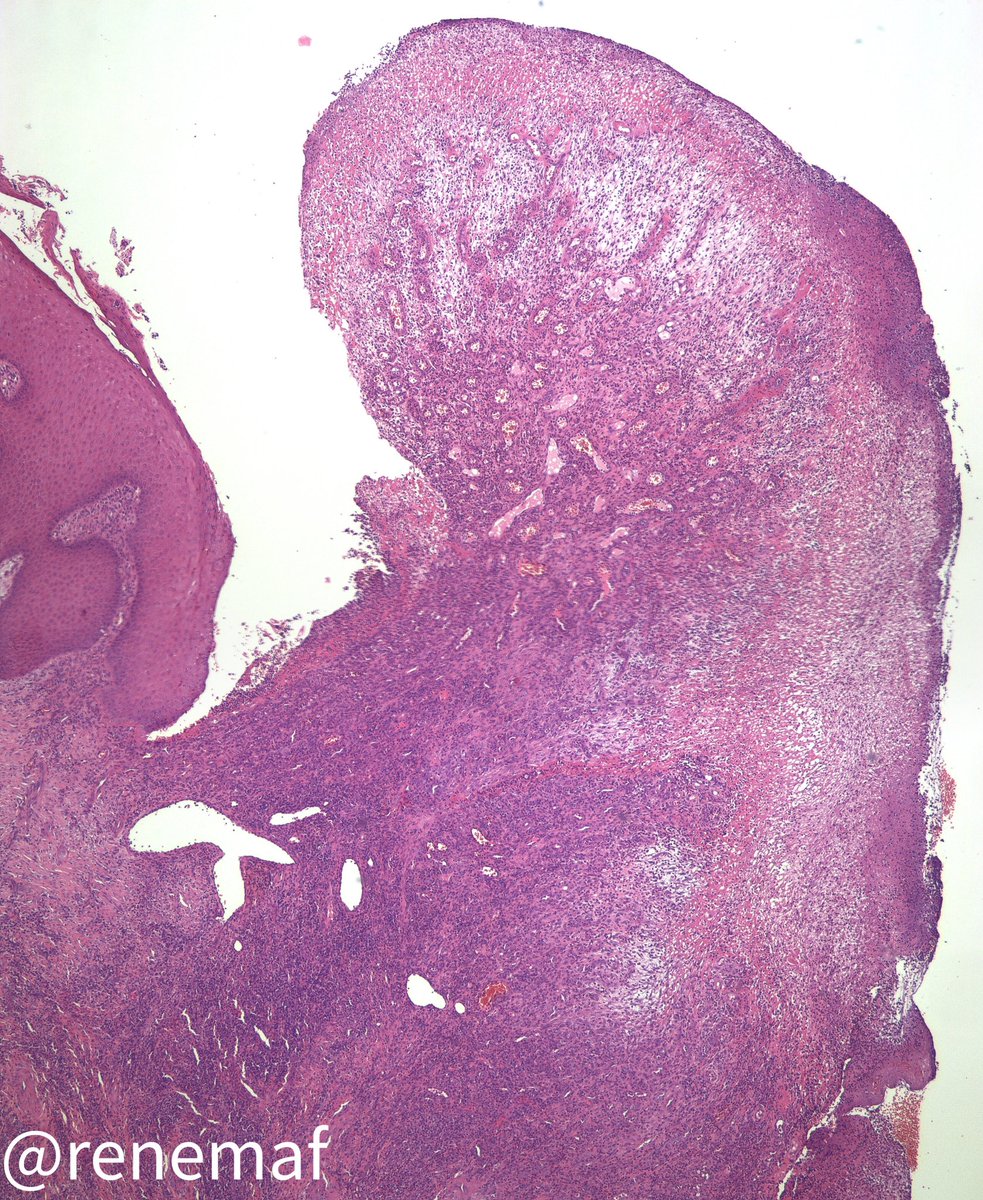

A 3 months in duration painful ulcer in a 58-yo female, without relevant medical history. An incisional biopsy was perfomed. What are you thinking ? Spot diagnosis? #oralpath #oralpathology🔬 #oralmed #oralmedicine 👀